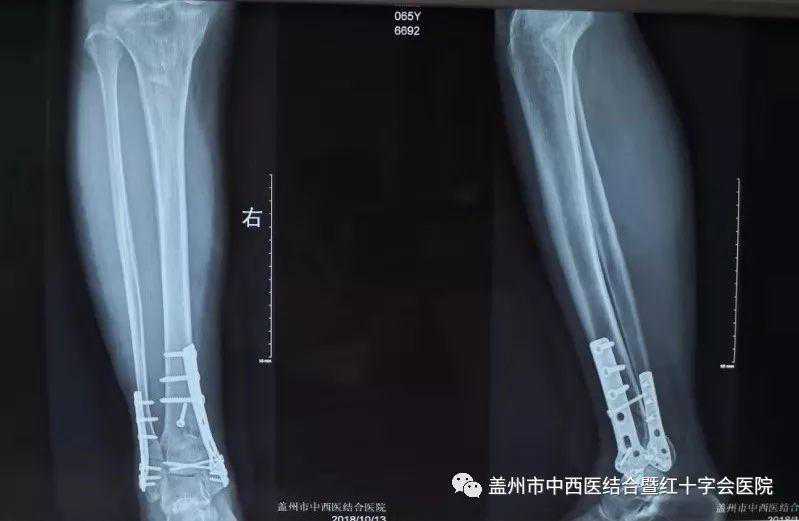

10月12日,盖州市中西医结合医院骨三科主任陈永博,在骨科专家施继明的指导下,成功为一名右胫腓骨远端粉碎性骨折的病人实施了切开复位钢板螺钉内固定术,术后效果非常好。据业内人士了解,该手术具有很高的技术含量,难度系数较高。

钢板螺钉内固定术这种内固定术多用于长管骨骨折,比较牢靠,临床应用较多。